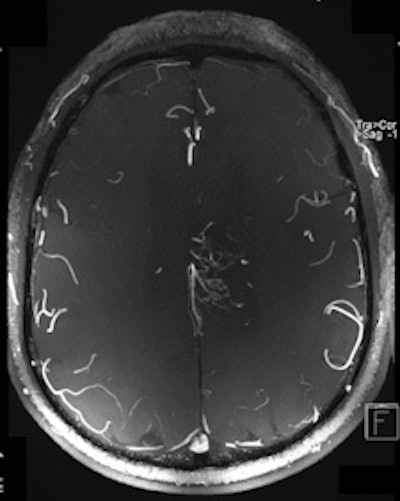

| Two 7-tesla images of a glioblastoma patient. Left: T2-weighted image shows brain lesion with very high spatial resolution. The heterogeneity in the lesion is already visible. Right: Time-of-flight MR angiogram shows the arterial vessels at the periphery of the lesion. The irregular vessel structure indicates neoangiogenesis, and it would be very interesting to see whether this vascular structure changes under new forms of neoangiogenic therapy. Image courtesy of Dr. Michael Bock. |

"High-resolution MRI in the brain, and in other anatomical areas (e.g., the knee), will become the first established clinical applications of high-field MRI," he said. "For example, we are able to visualize the tiny neovasculature in brain tumors, so high-field MRI might be a powerful tool to assess therapy response to the more and more popular neoangiogenic treatment," he commented.

Operating at increased magnetic fields makes it easier to obtain T2* contrast-enhanced images and improved implementation of susceptibility-weighted imaging, in which the phase of gradient-echo images provides information about local variation of magnetic susceptibility, according to Richard Bowtell, a professor from the Magnetic Resonance Centre, School of Physics and Astronomy, at the University of Nottingham in the U.K. In the brain, such variation appears to be dominated by differences in iron concentration and myelin content, so that high-field SWI may provide useful information about the progression of neurodegenerative disease. The elevated T1 relaxation times at 7-tesla also offer benefits for arterial spin labeling and time-of-flight angiography.